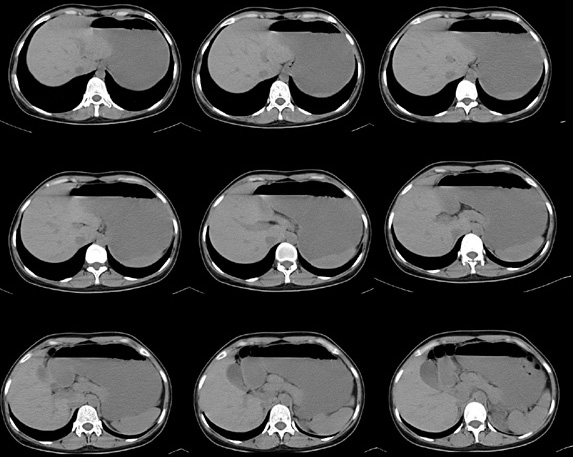

女性,28岁,停经3月,腹部膨隆1月,产前检查发现腹部占位

{肿块中心ct值27hu,增强后,动脉期、门脉期均无明显强化)

患者手术病理:腹腔囊性淋巴管瘤,象这样充满整个腹腔的的确很少见